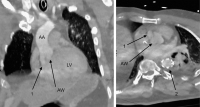

Abbildung 3: Postinterventionelles Kontroll-CTA nach TEVAR: AA – Aorta ascendens; LV – linker Ventrikel; AW – Aortenwurzel; 1 – Pseudoaneurysma im Bereich des nonkoronaren bzw. rechtskoronaren Sinus; 2 – expandierter Stentgraft in der proximalen Aorta descendens